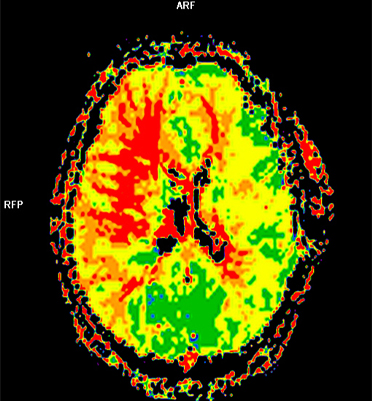

모야모야병의 확진 및 치료 계획을 세우기 위해서는 정밀 검사가 필요합니다. 모야모야병은 뇌혈관 자기공명검사(Brain MRA)나, 뇌혈관 컴퓨터단층촬영검사(Brain CTA), 뇌혈관조영술로 진단할 수 있습니다. 두개내 양측 내경동맥 말단부위나 주요 가지 동맥들의 점차적인 폐쇄로 인해 모야모야혈관이 자라나게 되는 특징적인 소견을 통해 진단을 내리고, 뇌혈역학적 검사(SPECT)를 통해 혈역학적인 스트레스 정도를 평가하게 됩니다. 최근에는 모야모야병 진단과 예후 및 가족형 모야모야 진단을 위해 RNF213이라는 유전자검사를 시행하고 있습니다.

두개내외 뇌혈관우회로수술, 수술 후 뇌혈관조영술 및 뇌관류CT

수술받은 좌측 대뇌반구는 뇌혈류 개선으로 인해 혈류감소를 의미하는 빨간색깔 부위가 사라집니다.